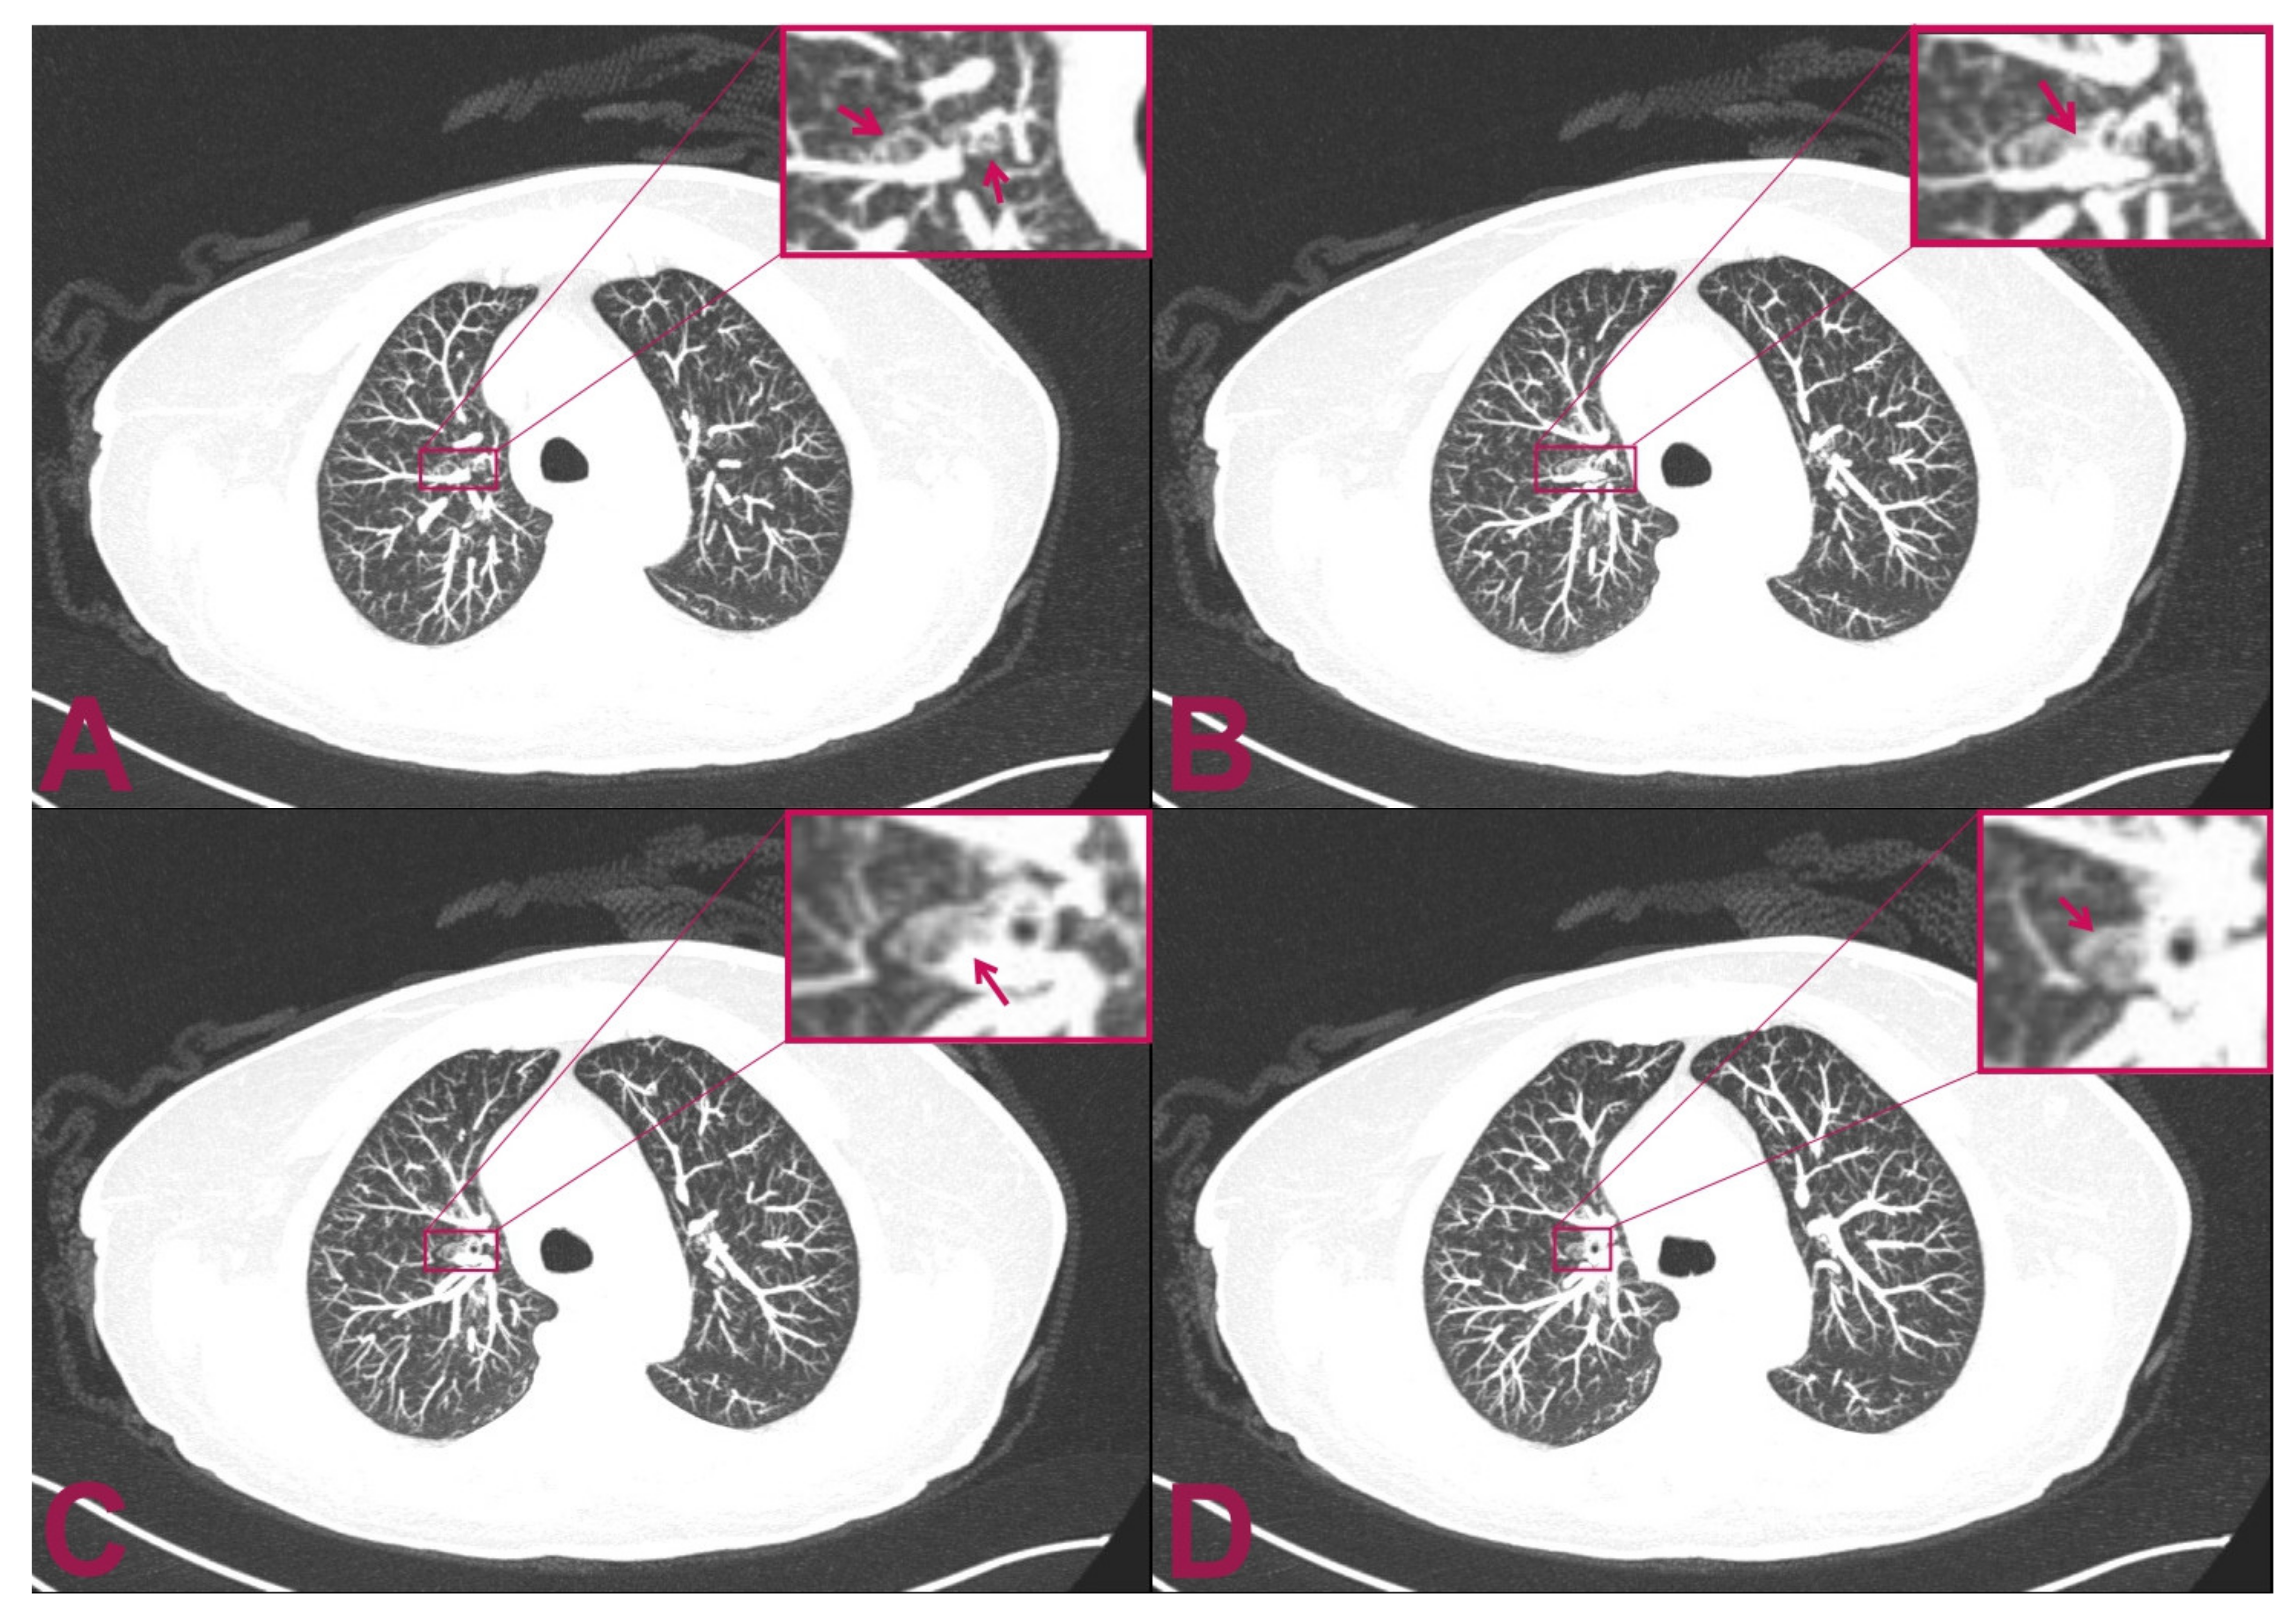

These findings highly suggest the presence of a poorly differentiated lung small-cell neuroendocrine carcinoma. The strong signal for the TTF1 marker is indicative of lung origin. The negativity for the CK20 marker is helpful for the differential diagnosis of the other metastatic small-cell neuroendocrine carcinomas, such as Merkel cell carcinoma, which would result as being positive for CK20 (Figure 2).

Figure 2. Histologic examination. (A) H.E.— small-cell carcinoma infiltrating nervous tissue. The cells have small, intense hyperchromatic nuclei, rounded and polygonal-shaped, and scant cytoplasm. Occasionally, it is possible to note “moulding” signs among the nuclei (arrow). (B) H.E.— in some areas, the nuclei have elongated shape (“fusiform”) or squashed (arrows). (C) Pan-cytokeratin (clone AE1/AE3)— the cytoplasm of the tumour cells are positive for cytokeratin. Staining for pan-cytokeratin, such as AE1/AE3, helps demonstrate that the tumour is a carcinoma rather than a lymphoid lesion (pan-CK negative and CD45 positive). (D) Positivity for cytokeratin 7 (CK7). Small-cell lung carcinoma (SCLC) is usually positive for CK7 and negative for CK20. About half of SCLC stain with CK7 and <10% with CK20. (E) Transcriptional Thyroid Factor 1 (TTF1)— strong positivity for TTF1 in almost all neoplastic cells is characteristic, but not specific, for small-cell carcinoma of the lung. Although the stain is less intense, it can be positive in 44–80% of extrapulmonary small-cell carcinomas. (F) Chromogranin A— dot-like granular positivity for chromogranin A is a marker of neuroendocrine differentiation of the neoplasm. Up to two-thirds of SCLC are negative for chromogranin and synaptophysin. When these markers are positive, this means that they have high specificity for neuroendocrine differentiation, unlike CD56, which is highly sensitive but not very specific. CD56 will stain approximately 90–100% of cases; however, it is less specific. The interpretation for SCLC diagnosis needs to be performed carefully in the appropriate morphological context and characteristics.

The histological analysis showed nervous tissue infiltration by poorly differentiated malignant carcinoma cells. These consist of epitheliomorphic cells, which are characterised by poor cytoplasm and medium-sized nuclei. In addition, frequent cellular spindling was present, as well as nuclear moulding and necrosis. The histologic examination was confirmed by immunohistochemistry, which resulted in CKAE1AE3++/CK7+/GFAP-/pS100-/HMB45-/TTF1++/chromogranin A + (dots on 60% of cells).